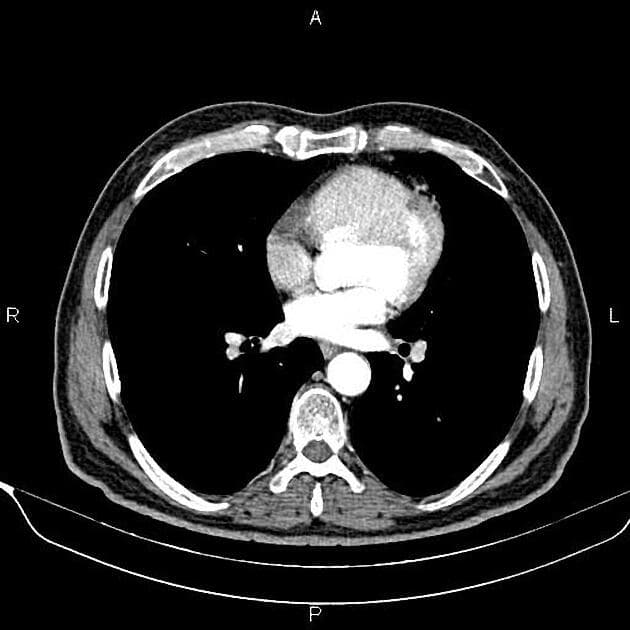

Axial C+ portal venous phase

- Khối dạng polyp ở đầu tụy gây giãn cả đường mật trong gan và ngoài gan.

- Khối dạng polyp ở đầu tụy (polypoid mass in the pancreatic head)

- Giãn đường mật trong gan và ngoài gan (dilated both intra- and extra-hepatic biliary ducts)

Khối dạng polyp ở đầu tụy đã được chứng minh trên mô học là u tuyến ống tụy (pancreatic tubular adenoma).

U tuyến ống tụy là một khối u lành tính hiếm gặp bắt nguồn từ biểu mô ống tụy, thường thấy ở đầu tụy. Khối u thường biểu hiện như một khối dạng polyp và có thể gây tắc mật, vàng da do nằm gần nhú tá lớn. Trên hình ảnh học, khối u hiện diện như một tổn thương ranh giới rõ, tăng tỉ trọng ở đầu tụy kèm giãn đường mật. Mặc dù các đặc điểm hình ảnh có thể giống với các tổn thương ác tính như ung thư biểu mô tuyến ống tụy hay u nhầy nội ống tụy (IPMN), bản chất lành tính được xác nhận bằng giải phẫu bệnh với cấu trúc tuyến dạng ống không có dị sản đáng kể. Cắt bỏ hoàn toàn khối u thường mang lại kết quả điều trị triệt để và tiên lượng lâu dài rất tốt.